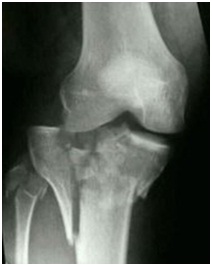

Se trata de masculino de 38 años de edad quien acude al

servicio de emergencias posterior a hecho vial tipo colisión moto-carro. Siendo

este el chofer de la moto, hecho ocurrido hace 3 horas presenta:

politraumatismos generalizados entre ellos destaca el trauma abdominal cerrado

y una fractura de platillo tibial tipo VI de Schatzker abierta tipo II derecha.

Según la clasificación de Gustilo;